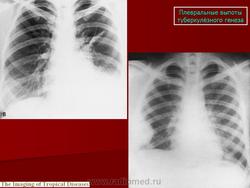

Туберкулёз плевры и грудной стенки

Приложения:

3.cover_.giff33.mediumplevry_i_grudnoy_stenki_tuberkuleza.giff34.mediumplevry_i_grudnoy_stenki_tuberkuleza.gif